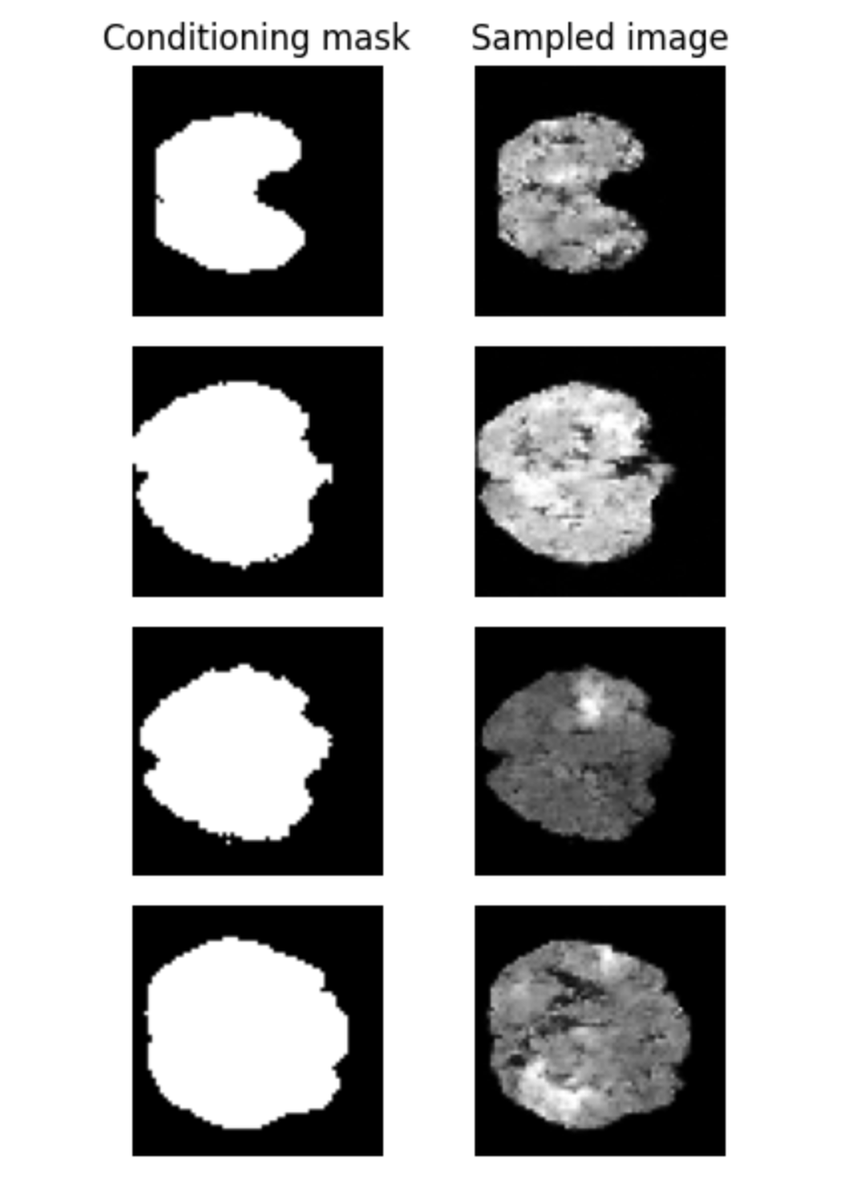

The ControlNet tutorial in MONAI Generative walks you controlling the shape of brain MRI samples with a supplied brain mask. Check it out!

ControlNet is a structure to control diffusion models by adding extra conditions proposed by @lvminzhang. Thanks to @marksgraham_ and @vir_fgcarmena, now we have a tutorial on controlnets to generate brain images. Check it out on MONAI Generative Models!